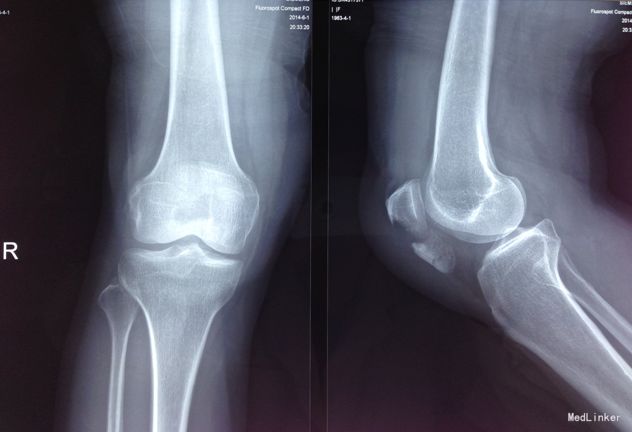

主诉:右膝关节疼痛活动受限12小时。现病史:患者于12小时前工作时不慎摔倒致右膝关节疼痛肿胀活动受限,遂前往 市四院行X线检查(2014-06-01)示右髌骨骨折。现为近一步治疗,来我科。入院后神志清楚,无发热,无胸闷气短,二便未见异常。

专科查体:右膝关节小夹板固定,右髌骨处软组织肿胀,右膝关节活动受限,右下肢皮肤感觉可,右下肢活动可,肌4级。右下肢足背动脉搏动良好,末梢血运良好,皮温正常。